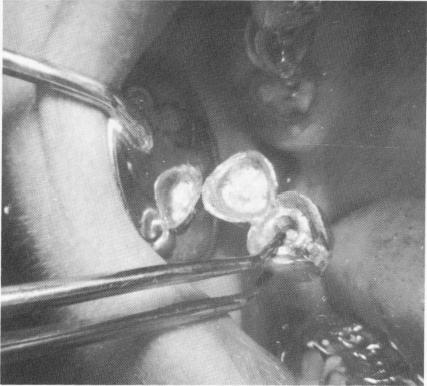

Fig. 15-65. The superstructure was then cemented over the built-up acrylic core and gold post extending from the template.

1 Implant superstructure cemented on acrylic core, gold post on template